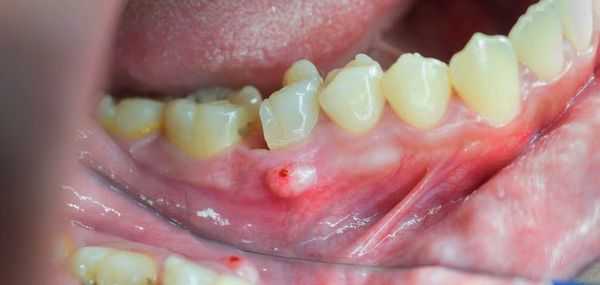

После острой стадии наступает подострая. На десне образуется гнойничок или свищ, через который гнойные выделения и воспалительная жидкость выходят наружу.

При осмотре полости рта заметны покраснение и отёк слизистой оболочки в области больного зуба и близлежащих тканей. Зуб разрушен, подвижен при пальпации, боль усиливается при постукивании по нему. Подвижными и болезненными также могут быть несколько неповреждённых зубов в зоне поражения.